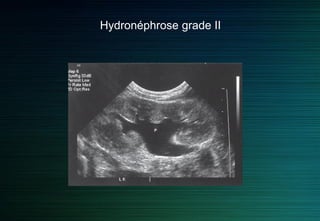

On différencie quatre grades d’hydronéphrose sur des critères échographiques

Grade 1 : dilatation du bassinet sans dilatation calicielle et épaisseur parenchymateuse normale.

Grade 2 : dilatation du bassinet et des calices avec amincissement du parenchyme.

Grade 3 : dilatation kystique du bassinet avec fin anneau du parenchyme.

Grade 4 : plus de parenchyme visible.

Hydronéphrose grade II